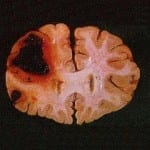

Antiinflamatórios, Enxaqueca e Risco de Derrame (AVC)